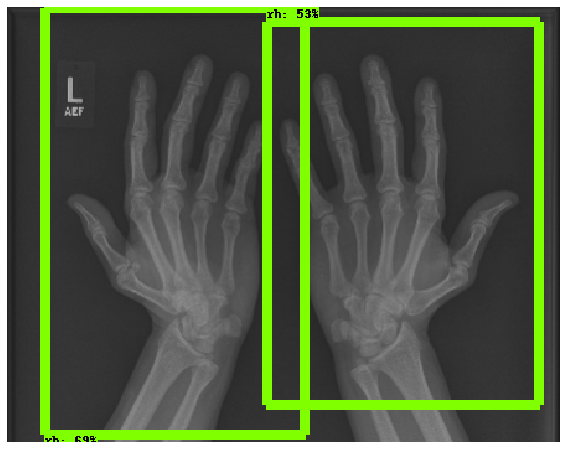

The first step in our pipeline is to detect the X-ray image carrier in the image. To this end, we apply OpenCV’s contour detection using Otsu binarization [14], and retrieve the minimum size bounding box, which does not need to be axis-aligned. This works sufficiently well as long as the majority of the image carrier is within the image (cf. Figure 3). However, the approach might fail for heavily tilted images or those where larger parts of the image carrier reach beyond the image border.

To further improve the detection of hands, and in particular split the images where two hands are depicted on one image, we manually labeled approximately 150 bounding boxes in the images. Using this small dataset, we fine-tune a pre-trained single shot multibox detector (SSD) [12] with MobileNet as taken from TensorFlow. An exemplary results can be seen in Figure 3.